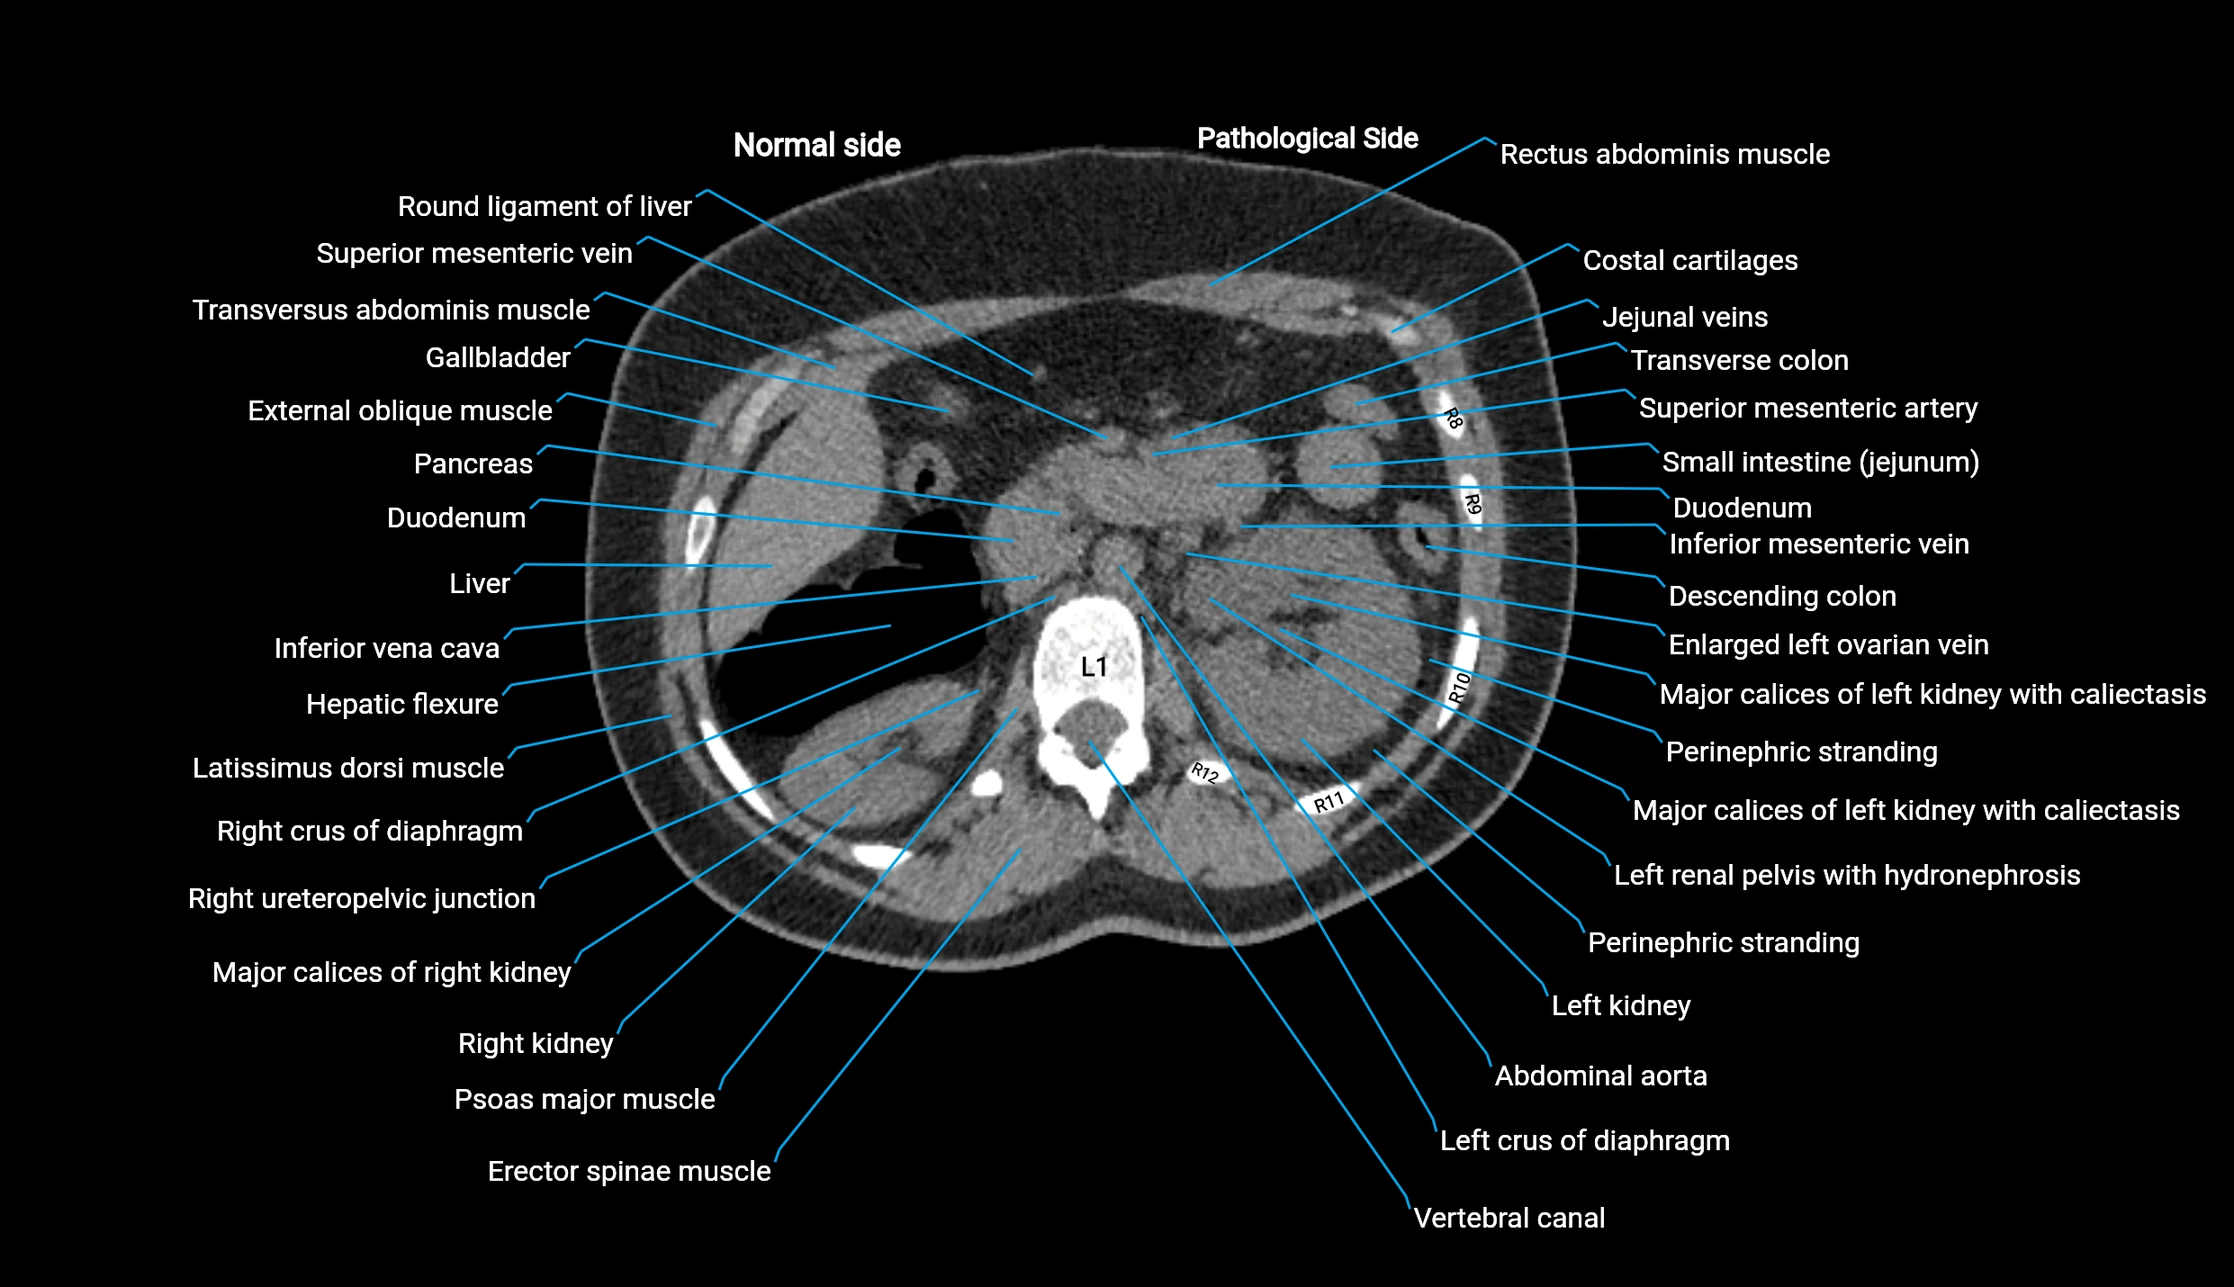

CT image

image